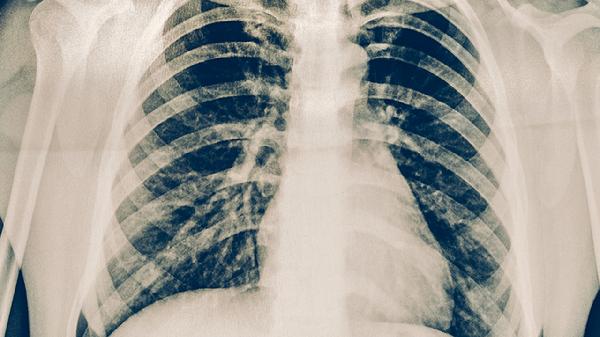

胸部X线检查是肺结核筛查的重要手段,可以发现肺部异常阴影。典型肺结核X线表现为上肺野浸润性病变、空洞形成或纤维钙化灶。但X线检查特异性较低,某些肺炎、肺癌等疾病也可能出现类似表现。对于X线检查异常者,需要结合其他检查结果综合判断。